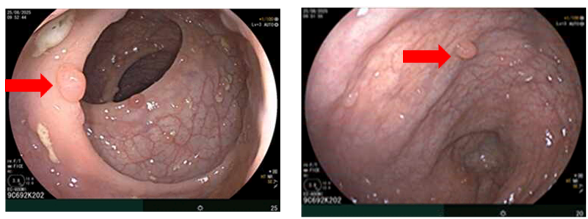

– Nội soi đại tràng: Phần quan sát được: Dọc đại tràng có nhiều polyp, tập trung ở đại tràng sigma kích thước ~ 0.3- 0.6 cm. Trực tràng có nhiều polyp kích thước ~ 03-0.6 cm.

Hình 3. Hình ảnh các polyp rải rác ở đại tràng (mũi tên đỏ)